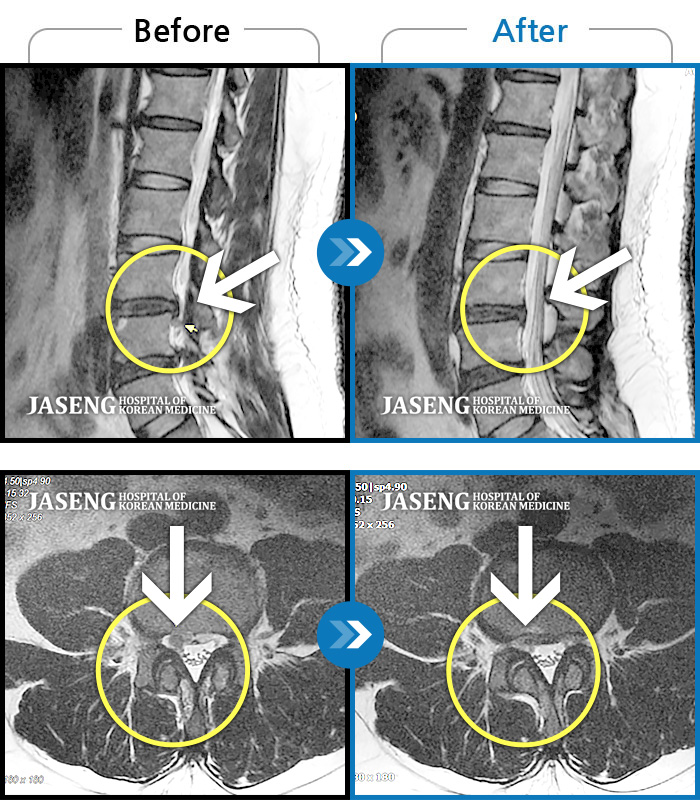

MRI 치료사례

앉았다 일어나면 통증 발생, 앉아서 근무할 때 다리 저림